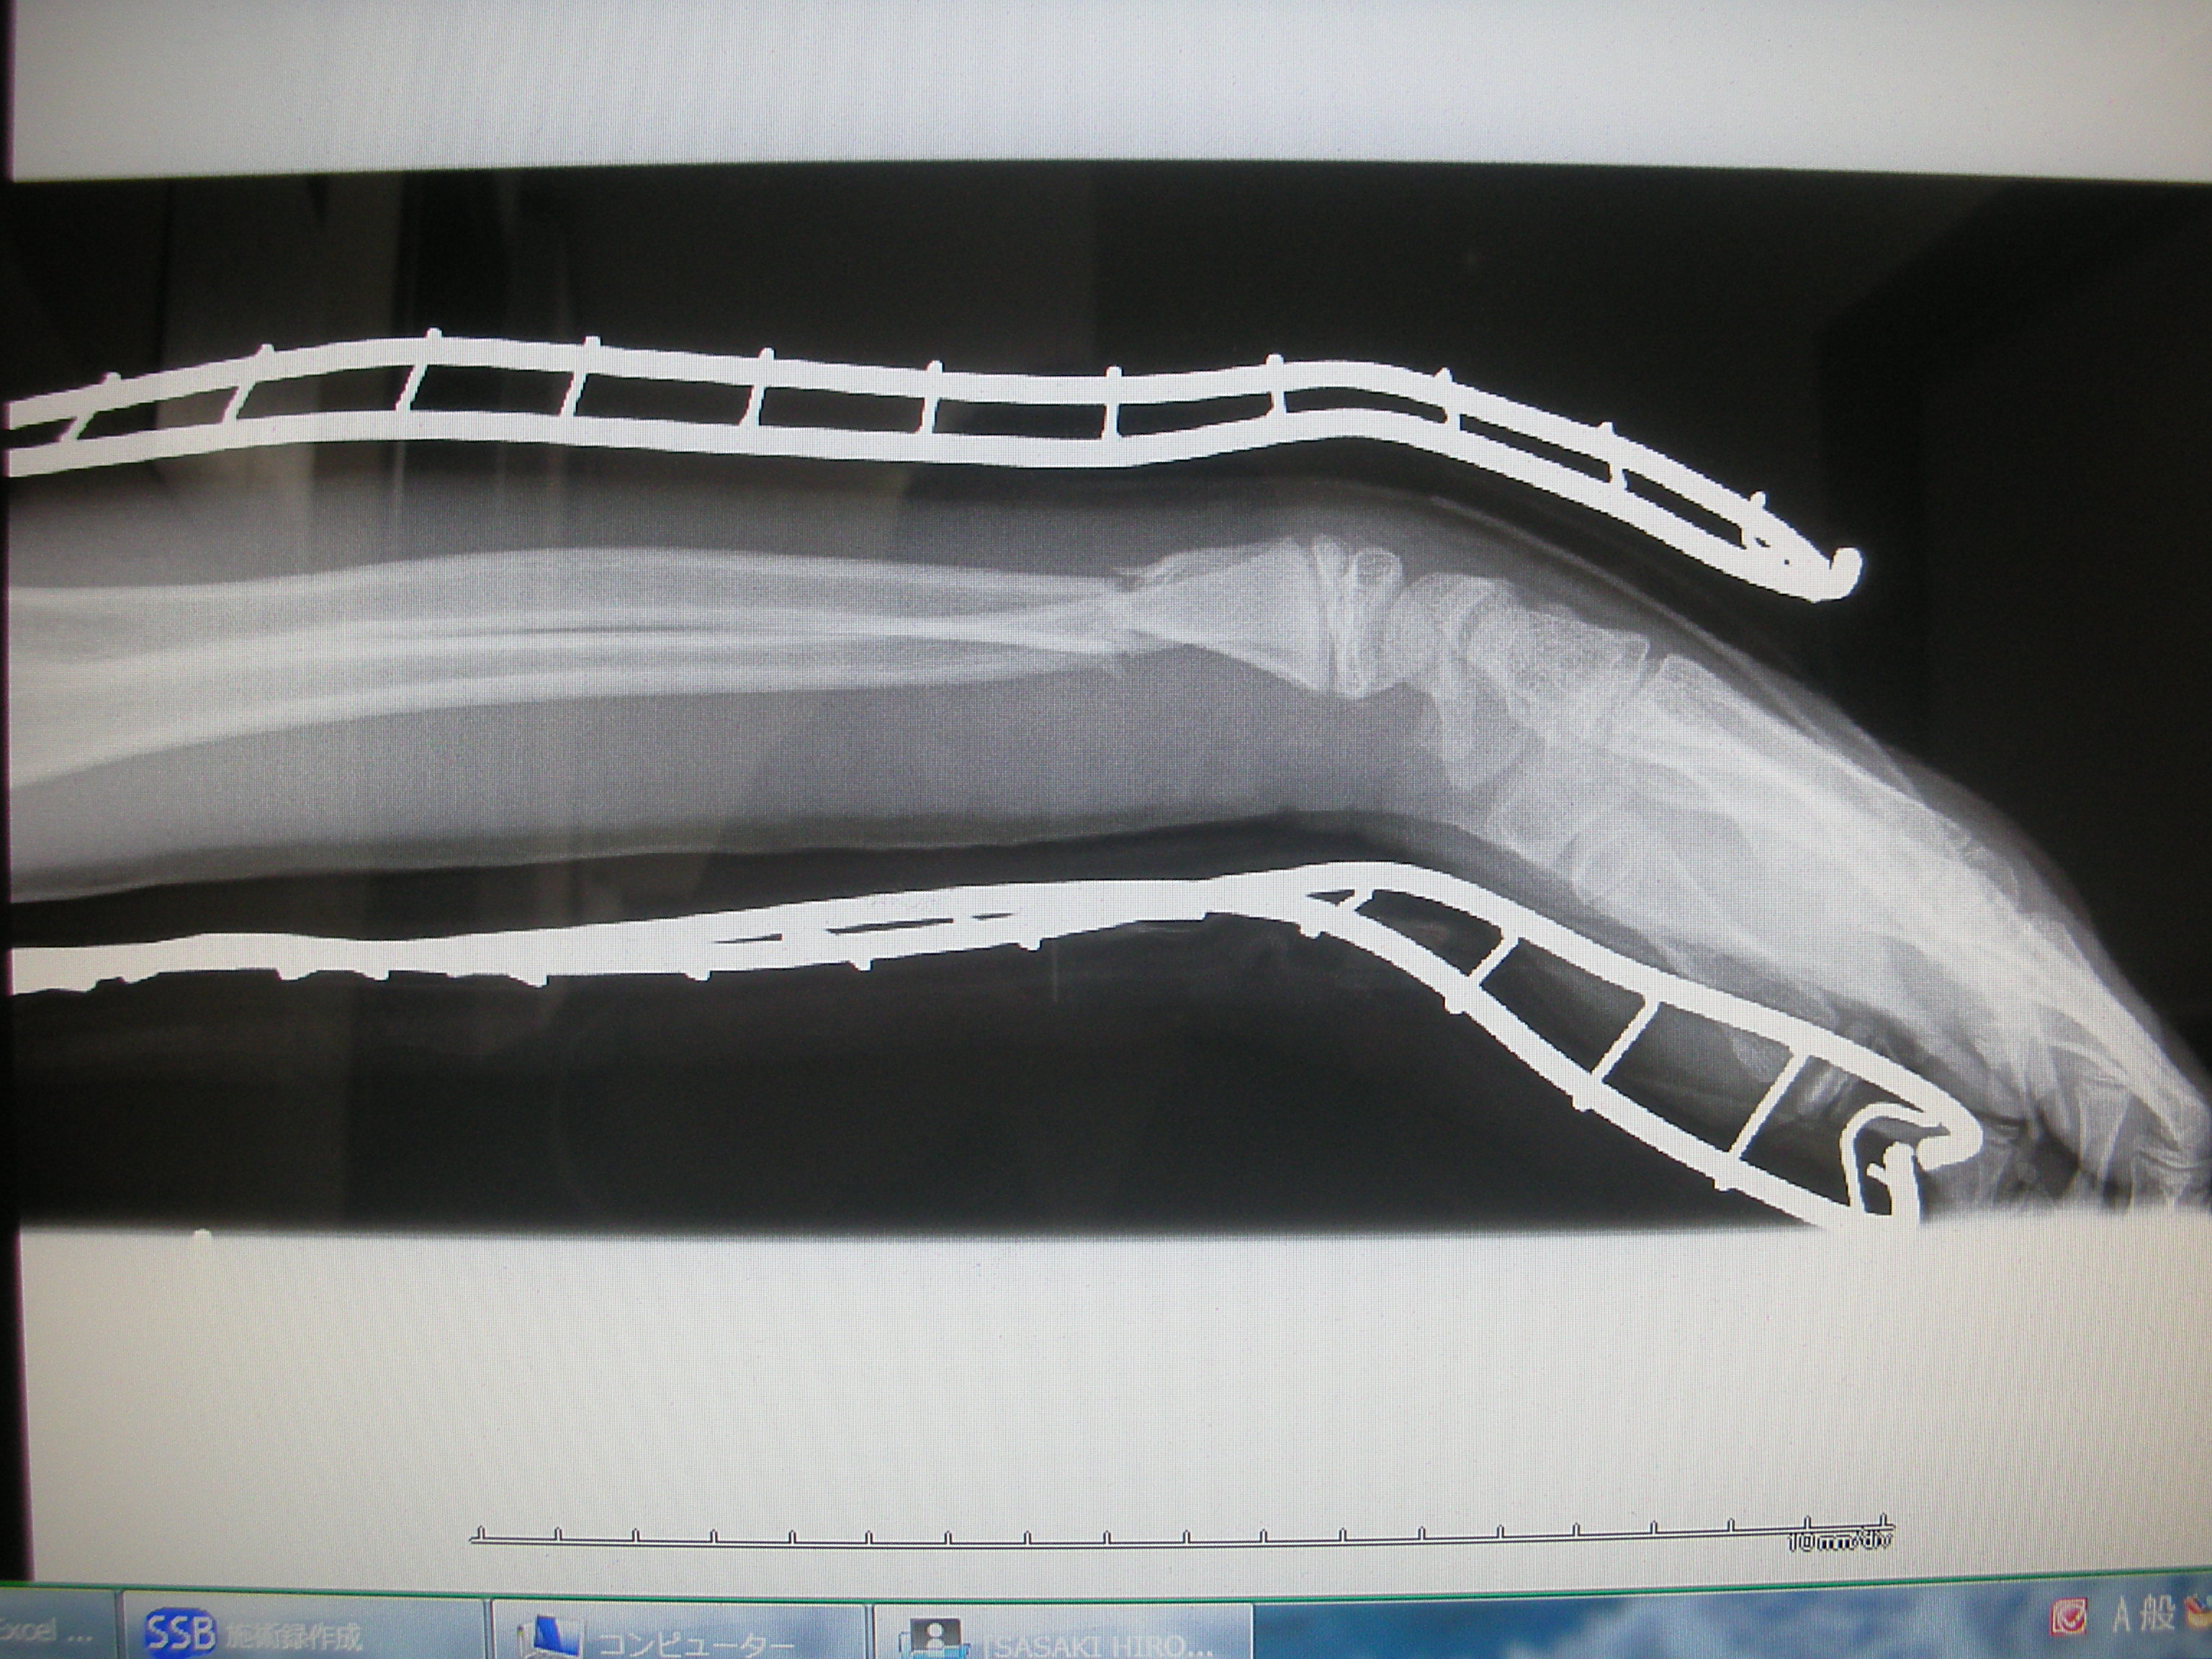

整復・固定の実際をいくつか紹介します。